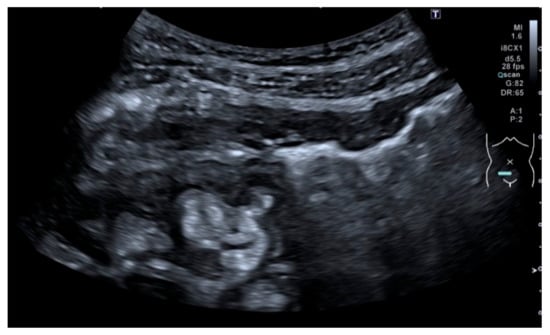

Depending of the CD phenotype, different ultrasonographic characteristics can be identified. The presence of ulcers can be visualized as depressions in the mucosal layer. Strictures are characterized by wall thickening with a narrowed lumen, with or without a dilatation of the proximal loop (pre-stenotic dilatation) (see Figure 5). The fistulae are seen as hypoechoic peri-intestinal areas with diameter < 2 cm with or without internal gaseous artifacts. Abdominal abscesses are seen as hypo-anechoic lesions containing fluid and gaseous artifacts, posterior enhancement, irregular margins sometimes within hypertrophic mesentery, without vascular signals at color Doppler (see Figure 6). An inflammatory mass is seen as an irregular hypoechogenic lesion, with vascular signals at color Doppler.

Figure 5.

Detection of complications: stricture with pre-stenotic dilation: Strictures are characterized by a wall thickening with a narrowed lumen, with or without a dilatation of the proximal loop (pre-stenotic dilatation).